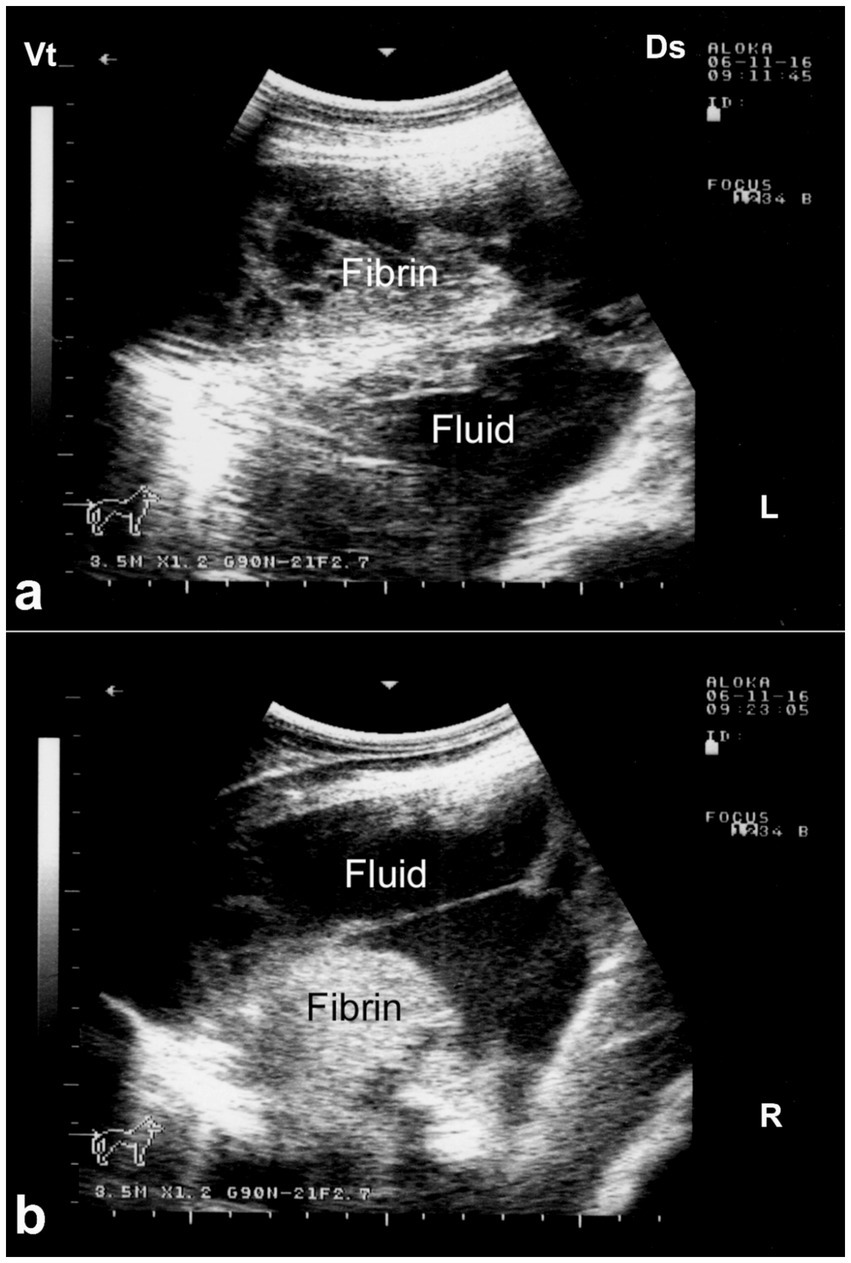

Ultrasonography is considered the most reliable and practical tool for diagnosing pleural effusion in camels, particularly in the absence of accessible radiographic facilities. Sonographic findings typically include an anechoic or hypoechoic fluid accumulation between the visceral and parietal pleura, with displacement or compression of adjacent lung tissue. Fibrin strands, septations, and floating echogenic debris may also be visualized, particularly in exudative or chronic effusions (8). Ultrasonography not only enables accurate assessment of the volume and nature of pleural fluid but also guides safe and effective thoracocentesis, fluid sampling, or drainage procedures. Furthermore, it facilitates serial monitoring of disease progression and response to therapy, thereby enhancing clinical decision-making and prognosis (32). In dromedaries presenting with clinical signs of pleural effusion, ultrasonographic examination reveals hypoechoic to anechoic fluid within the pleural cavity, located between the parietal pleura, diaphragm, and lung. Echogenic strands or fibrin may be visible within this fluid. The accumulation of pleural fluid causes compression atelectasis, particularly in the cranial lung lobes, which appear hypoechoic. Entrapped air in larger bronchi appears hyperechoic and is often accompanied by comet-tail artifacts. Fibrin is visualized as thin, filamentous strands floating within the effusion, loosely attached to the pleural surfaces. It is also common to observe fluid pockets separated by fibrin strands (32) (Figure 12).

Figure 12. Ultrasonographic evidence of pleural effusion in a dromedary camel calf. (a) Longitudinal ultrasonographic image of the right hemithorax showing an anechoic pleural space between the collapsed lung surface and the thoracic wall, consistent with a free, transudative pleural effusion (PE). The underlying lung is partially visualized as a compressed, hypoechoic structure. (b) Left thoracic ultrasound image demonstrating fibrinous pleural effusion (FPE), characterized by multiple echogenic fibrin strands floating within the anechoic fluid. These suspended echogenic bands are indicative of an exudative or inflammatory process, typically associated with infectious pleuropneumonia. Ds – Dorsal; Vt – Ventral [modified from Tharwat (32)].

Ultrasonography plays a vital role in the evaluation of pleurisy and pleuropneumonia, particularly where clinical signs are ambiguous or overlap with other respiratory conditions. In pleuritic cases, ultrasound can detect pleural thickening, fibrinous adhesions, and comet-tail artifacts arising from inflamed pleural surfaces. When pleuropneumonia is present, additional sonographic findings may include hypoechoic areas of lung consolidation, hepatization of pulmonary tissue, and pleural effusion with echogenic debris or septations—hallmarks of exudative inflammation (8). Ultrasound not only enables differentiation between pleural and pulmonary involvement but also facilitates monitoring of disease progression, planning of therapeutic drainage procedures, and sampling for microbiological diagnosis (31, 32). Its utility in field conditions makes it an indispensable tool for timely and accurate assessment of pleuropulmonary diseases in camelids. Thoracic ultrasonography is a valuable tool for monitoring pleural and pulmonary changes. It facilitates the detection of pleural effusion and helps in assessing prognosis (7). Ultrasonographic findings may include anechoic fluid accompanied by fibrin networks between the right and left pleurae. In advanced cases, bilateral heterogeneous pleural effusions containing fibrin strands can be observed and confirmed by ultrasound-guided thoracocentesis (Figure 13). In more severe instances, significant amounts of heterogeneous fluid with extensive fibrin networks can be seen in both pleural sacs (Figure 14) (8).

Figure 14. Ultrasonographic findings of bilateral fibrinous pleuropneumonia in a dromedary camel calf. (a) Left thoracic cavity; (b) Right thoracic cavity. Both images demonstrate extensive, hyperechoic fibrin strands floating within anechoic to hypoechoic pleural effusion, consistent with severe fibrinous pleuritis. The heterogeneous echotexture of the pleural fluid and evidence of adjacent pulmonary consolidation suggest concurrent lung involvement [modified from Tharwat and Al-Sobayil (8)].